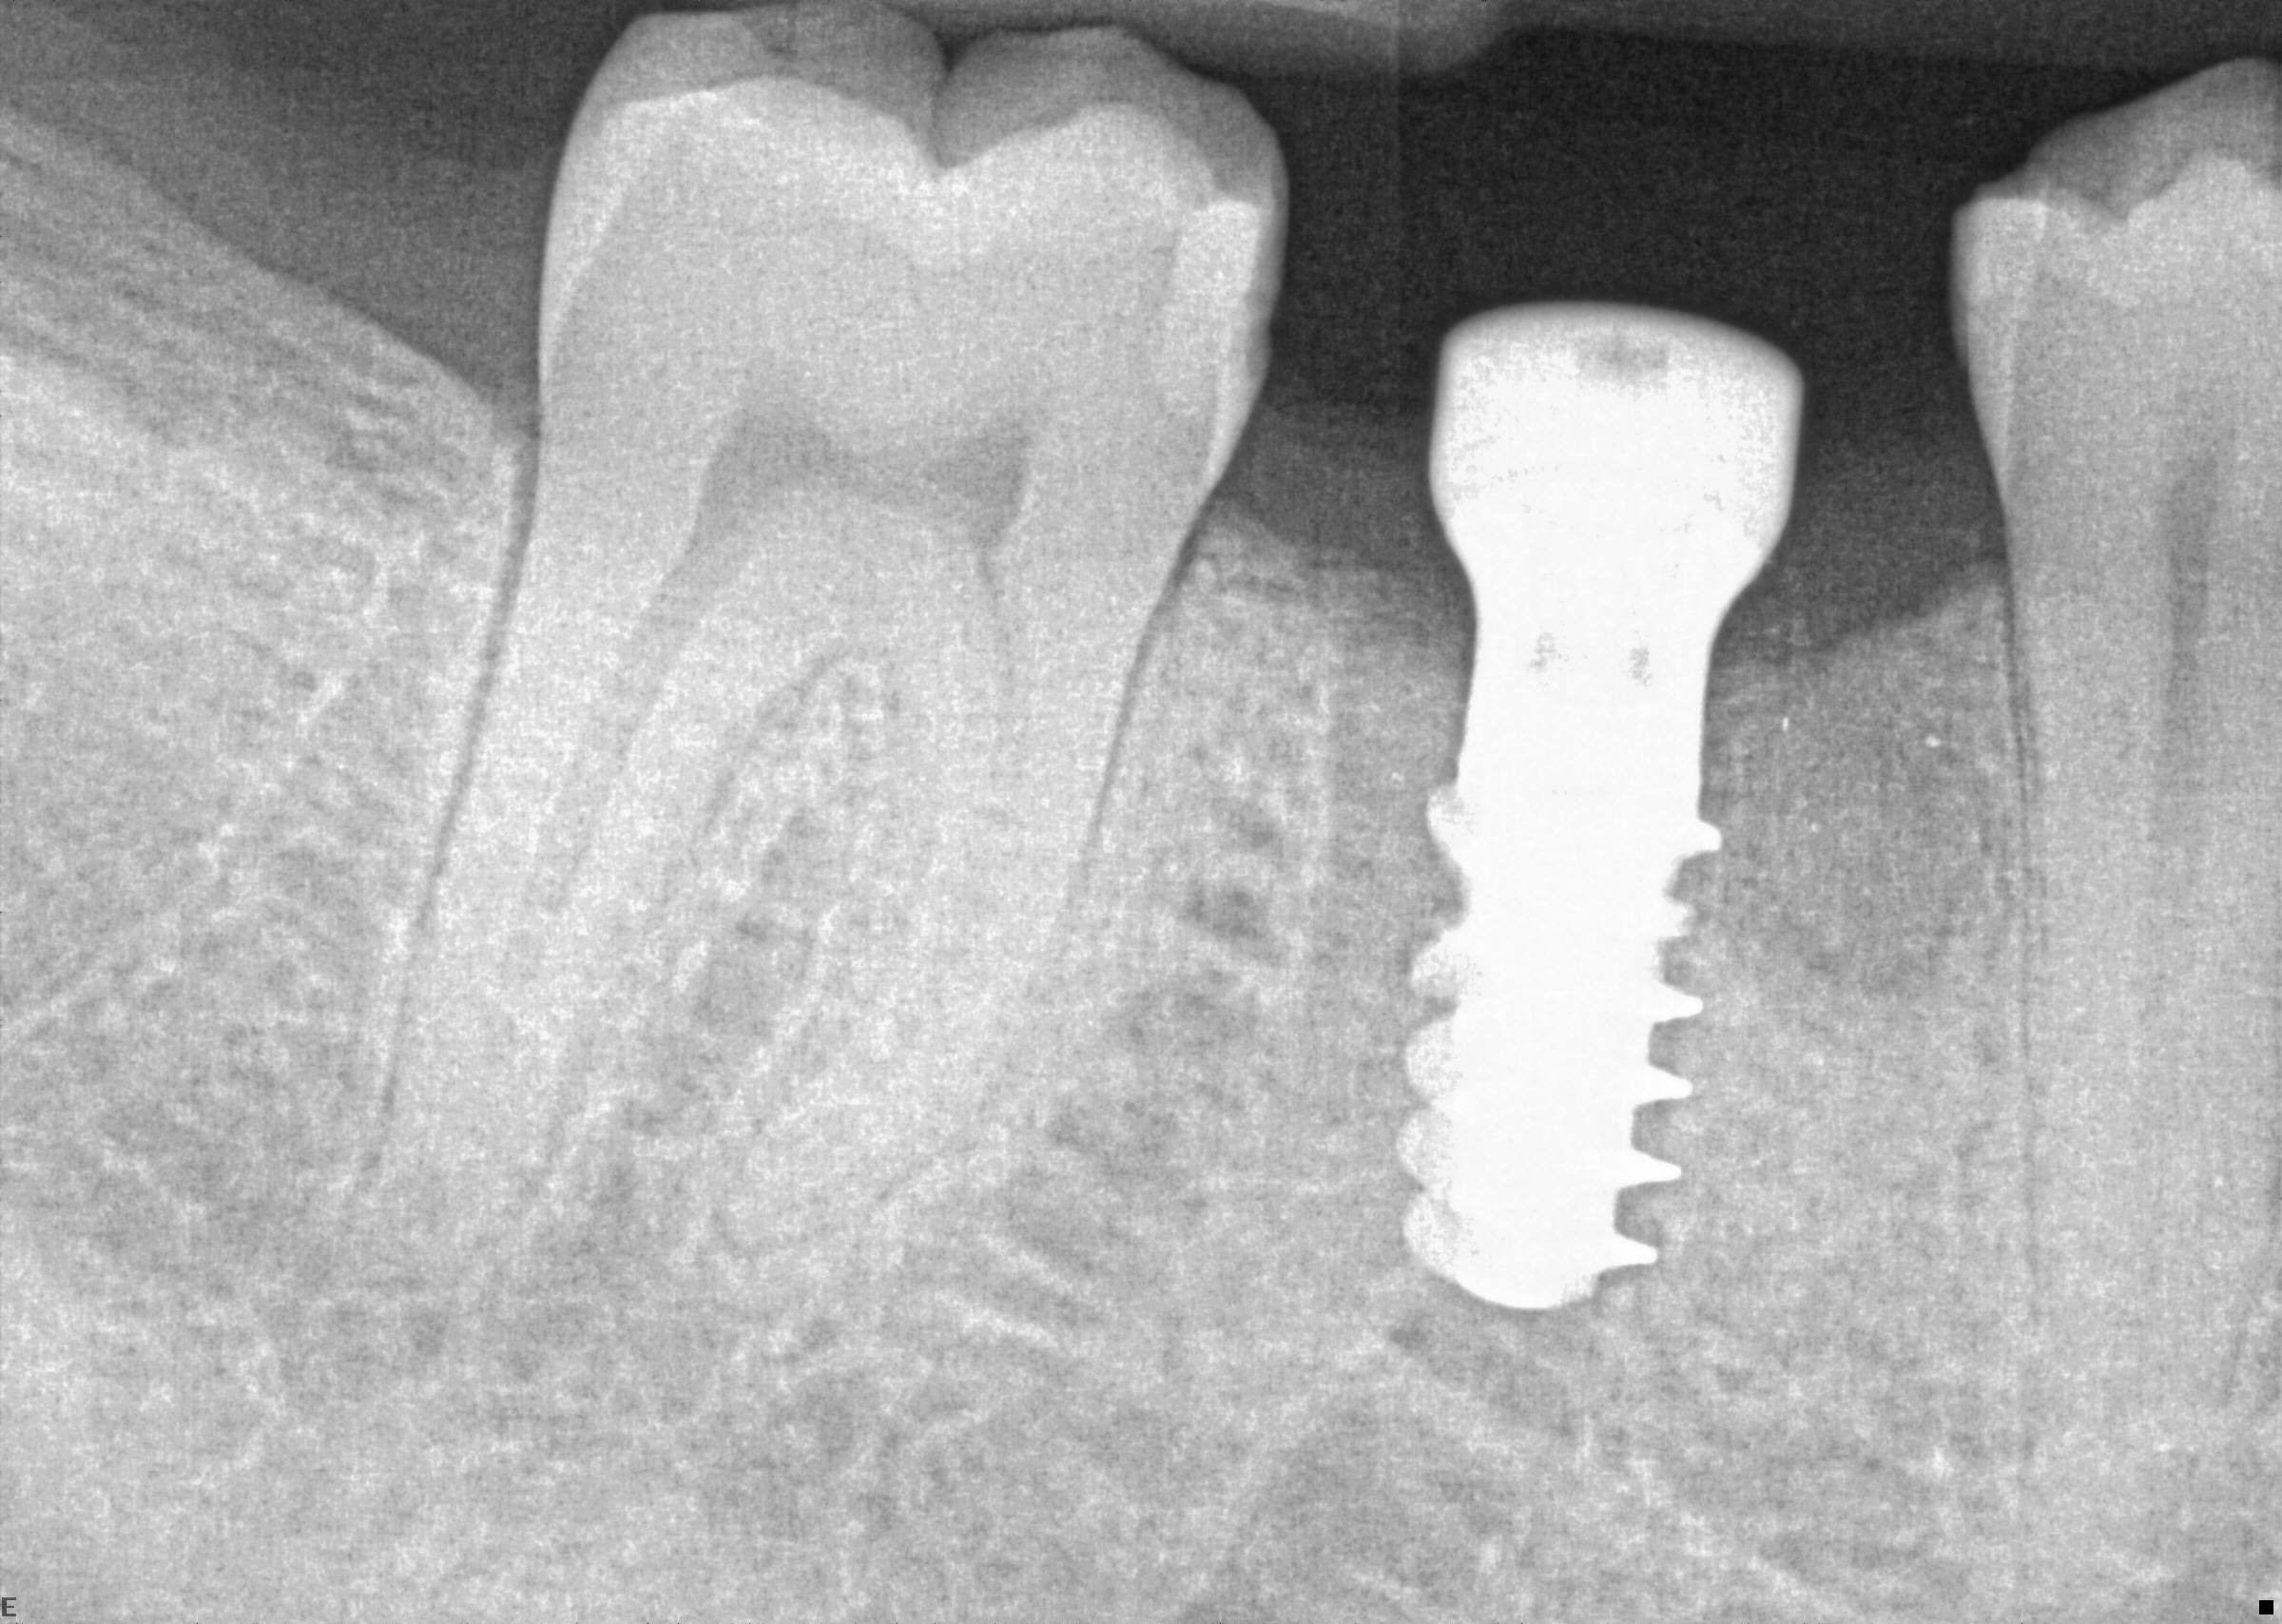

13. (Select ONE or MORE correct answer)

Which of the following is true regarding dental implant at site 2.6?